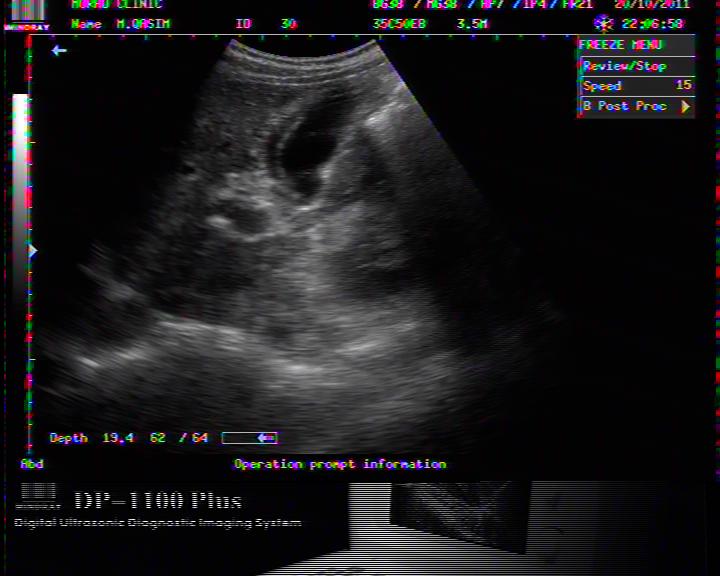

FLUID AROUND LIVER IN DHF

PLASMA FLUID AROUND LIVER IN DHF